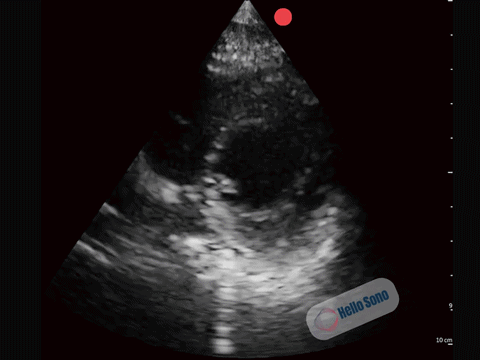

In a normal PSSA view:

- The left ventricle appears circular

- The interventricular septum maintains its natural curvature

- The right ventricle is clearly smaller than the left ventricle

The left ventricle should resemble a symmetric donut. When it takes on a D-shape, right-sided pressures are elevated.